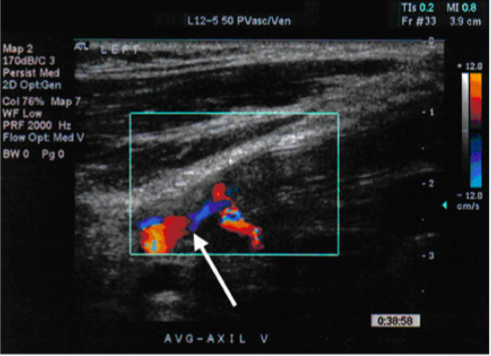

For the following arterial duplex US (DUS) image:

comment on the PRF setting

PRF is set very low

you can tell this based on the velocity range of the color bar (range of 12 cm/s, relatively low setting

recall that PRF value is directly-related to color doppler frequency parameters (and the associated blood velocity)